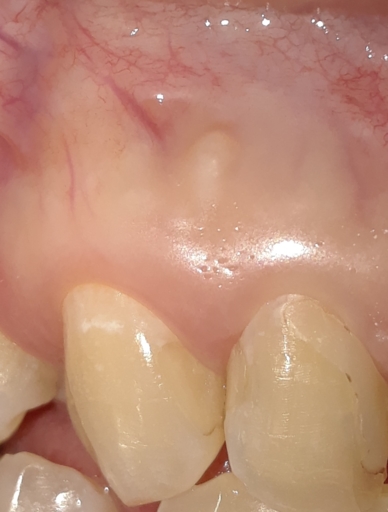

Had a root canal done almost a year ago but had the crown removed because food kept getting trapped underneath. It is tooth #29. It was omitting a bad smell from flossing the food out that kept getting trapped by the crown. Then I noticed on the xray theres a black space near the root. I asked the dental clinic where the root canal was done but seemed to avoid the question. Please see attached xray I did not want to put the permanent crown back on til I was certain but could not get a straight answer from my provider.

Unfortunately, I am unable to see the x-ray you submitted for tooth #29. However I do see the x-ray you submitted for the upper right tooth #3 which has a crown off and an existing root canal. Sometimes, a small black area around the apex of the root after a root canal can be a scar from the previous infection. It is hard to tell if it is a new infection, especially not being able to compare the pre-op and post-op x-rays. The large black space above the tooth is actually your sinus cavity. Any open space will appear more radiolucent (black) than for example, bone which is more dense. It is not a good idea to keep the crown off, the tooth is exposed and there is a risk of having a re-infection from the presence of bacteria. It is best to re-cement the crown even if it is with temporary cement to keep the tooth protected from bacteria, prevent the tooth from shifting and super erupting as well and worst case, fracture. These movements happen very quickly and will cause the crown to no longer fit the tooth. If the tooth were to fracture, there is a possibilty it would need to be extracted and a dental implant placed. It is better to be proactive in this situation.